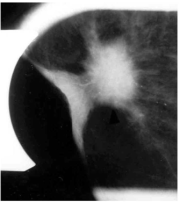

| 16:18, 5 בספטמבר 2012 | Breastcancer2412.png (קובץ) |  |

88 קילו־בייטים | Motyk | 1 | |